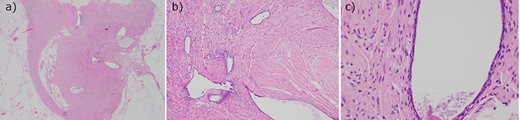

A 56 year old woman presented to emergency with seven days of abdominal pain. Her pain was initially dull and within the peri-umbilical region before migrating to the right iliac fossa and becoming sharp and constant. The pain was associated with subjective fevers and anorexia. There were no bowel or urinary symptoms reported. The patient was post-menopausal and before presentation was previously well with no significant past medical history; her only surgical history included two lower segment caesarean sections. She was seen by her general practitioner who arranged for an outpatient CT of the abdomen and pelvis with oral and intravenous contrast, undertaken on day six of symptoms. CT findings demonstrated a thickened appendix measuring up to 11 mm, reported as consistent with acute appendicitis. There was no significant fat stranding, intraperitoneal free fluid, nor gas, and the CT was otherwise unremarkable (Fig. 1). Upon presentation to emergency, examination found a clinically stable patient with tenderness in the right iliac fossa and suprapubic regions, particularly over McBurney’s point. Rosving’s sign was negative. White cell count was 6.8 × 109 cells/L, neutrophils 2.5 × 10^9 cells/L, C-reactive protein of 9.5 mg/L, while creatinine was slightly elevated at 96 μmol/L and electrolytes were within normal limits. She was incidentally found to be COVID-19 positive, however, was asymptomatic and was fully vaccinated. As her abdominal symptoms continued, she was taken to the operating theatre for a laparoscopic appendicectomy. This was completed unremarkably, with intra-operative macroscopic appearance of a thickened appendix without other abnormality, and the specimen routinely sent for histopathology. She was subsequently discharged from hospital without complication with resolution of her pain. Histopathology demonstrated mild acute mucosal appendicitis with occasional endometrial type glands with no stroma nor hemosiderin-laden macrophages, in keeping with endosalpingiosis (Fig. 2). There was no evidence of malignancy.

Histopathology of the appendix with hematoxylin and eosin stain demonstrating occasional endometrial type glands with no stroma or hemosiderin macrophages, in keeping with endosalpingiosis. Viewed in (a) low, (b) intermediate and (c) high magnification.